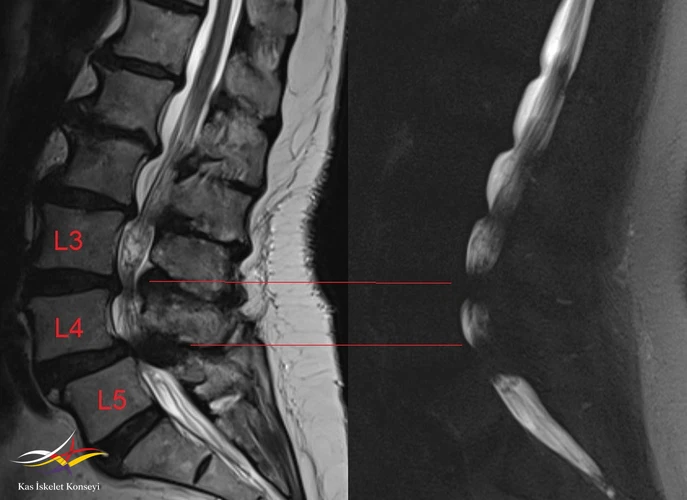

Resim 6. Sagitaal MRG ve MRG myelografide darlık seviyeleri.